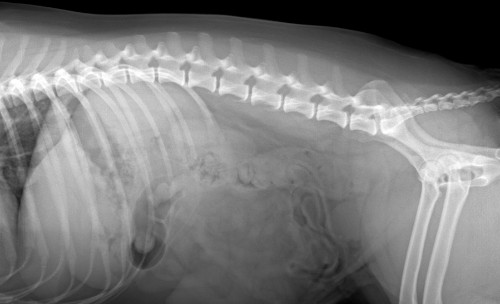

After Surgery